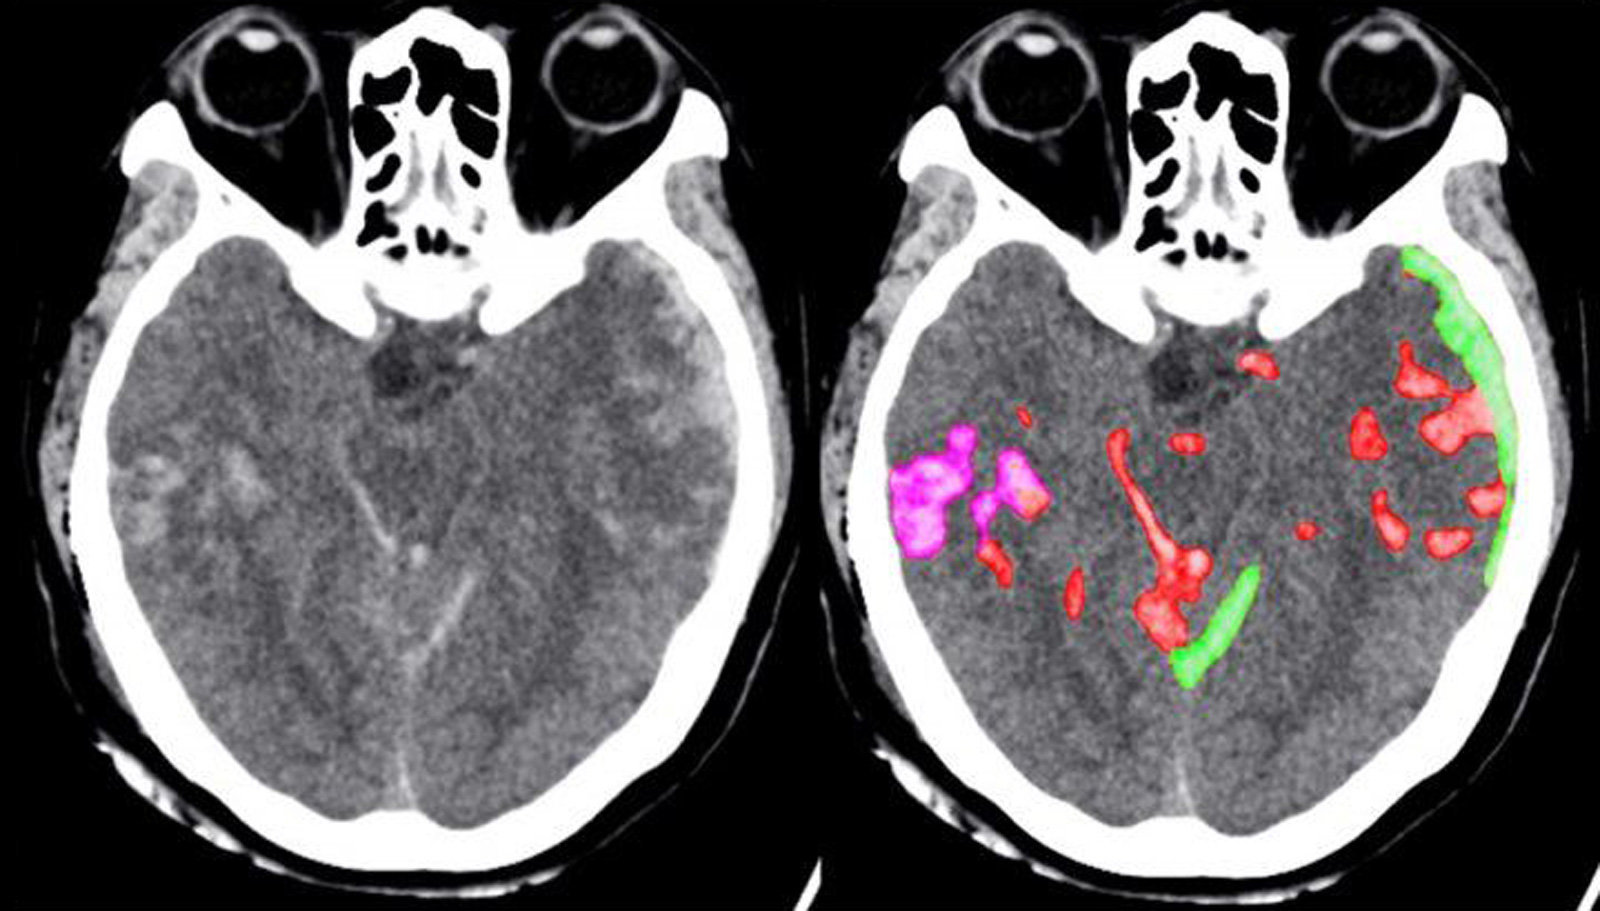

L’intelligenza artificiale può aiutare enormemente la diagnostica di emorragie non immediatamente visibili. È quanto emerso da uno studio congiunto delle università californiane Berkley e San Francisco, le quali hanno creato un algoritmo in grado di rilevare emorragie al cervello con una precisione migliore del 50% dei radiologi sottoposti al test.

In pratica l’intelligenza artificiale è in grado di diagnosticare un’emorragia cerebrale meglio di due dei quattro radiologi che hanno preso parte al test. Questo accade non perché siano medici incompetenti, tutt’altro: l’IA riesce però ad esaminare i risultati della TAC, o Tomografia Assiale Computerizzata, con una precisione che arriva al singolo pixel.

Così l’algoritmo riesce a non farsi distrarre dal rumore digitale o altri falsi positivi, ed il merito è dell’abbondanza di dati che i ricercatori delle due Università hanno “dato in pasto” all’intelligenza artificiale. In totale oltre 4.396 TAC sono state esaminate da una rete neurale convoluzionale, il cui funzionamento è ispirato a processi biologici. Le reti di questo tipo vengono spesso usate per il riconoscimento di immagini e video, in bioinformatica e nell’elaborazione del linguaggio naturale.

Ad esempio, un’intelligenza artificiale che usa una rete neurale di questo tipo è in grado di generare la foto di come verrà una pizza prima ancora che venga cotta. Nel caso della diagnostica di emorragie al cervello tramite intelligenza artificiale, l’IA è stata istruita per esaminare parti singole dell’immagine invece che l’intera TAC, così da ridurre le possibilità di falsi positivi e assunzioni non corrette basate su minuscoli cambiamenti.

Può l’intelligenza artificiale sostituire l’elemento umano nella diagnostica medica? Non ancora. L’algoritmo esamina una TAC e genera un report in un secondo, e può aiutare a scovare differenti tipi di emorragie. Questi risultati però vanno sempre avallati da dottori esperti: solo il lavoro di squadra tra nuovi strumenti e professionisti in carne ed ossa può portare a salvare vite, che in altri scenari potrebbero avere serie complicazioni.